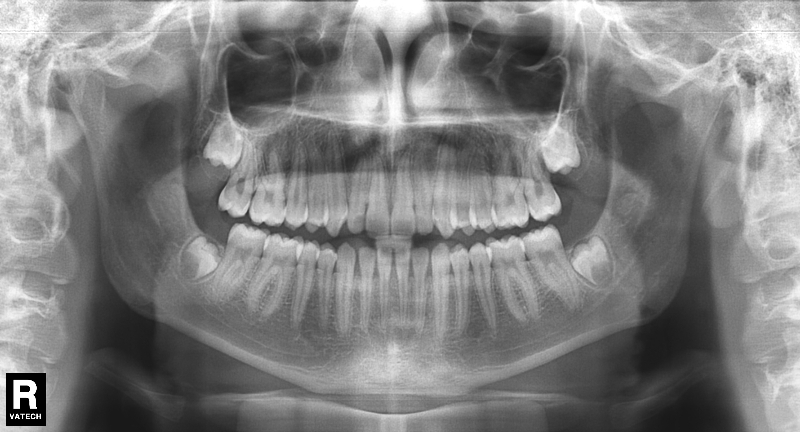

El paciente E.A. acude a nuestra consulta por diastema inferior y ausencia de contactos en los sectores laterales.

1) Arreglamos el problema funcional (lengua baja). Colaboramos con la logopeda Ana Muñoz.

2) Colocamos aparatología fija (brackets Damon) arriba y abajo.

El stripping consiste en la reducción interproximal del esmalte entre los dientes posteriores y anteriores, así obtenemos espacio para alinear los dientes apiñados.

Chica de 17 años tratada en 1 año con stripping en los dientes inferiores